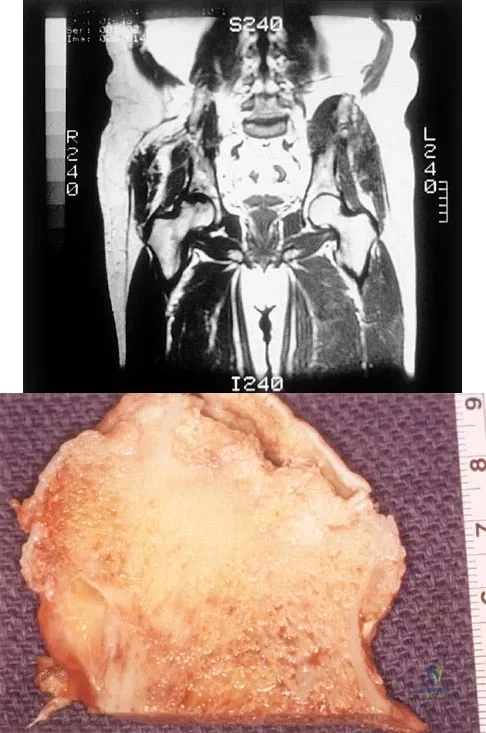

Question 35

A 42-year-old man reports the recent onset of right hip pain. A radiograph and MRI scan are shown in Figures 38a and 38b. A WBC count, erythrocyte sedimentation rate, and hip aspiration are within normal limits. Management should now consist of

Explanation